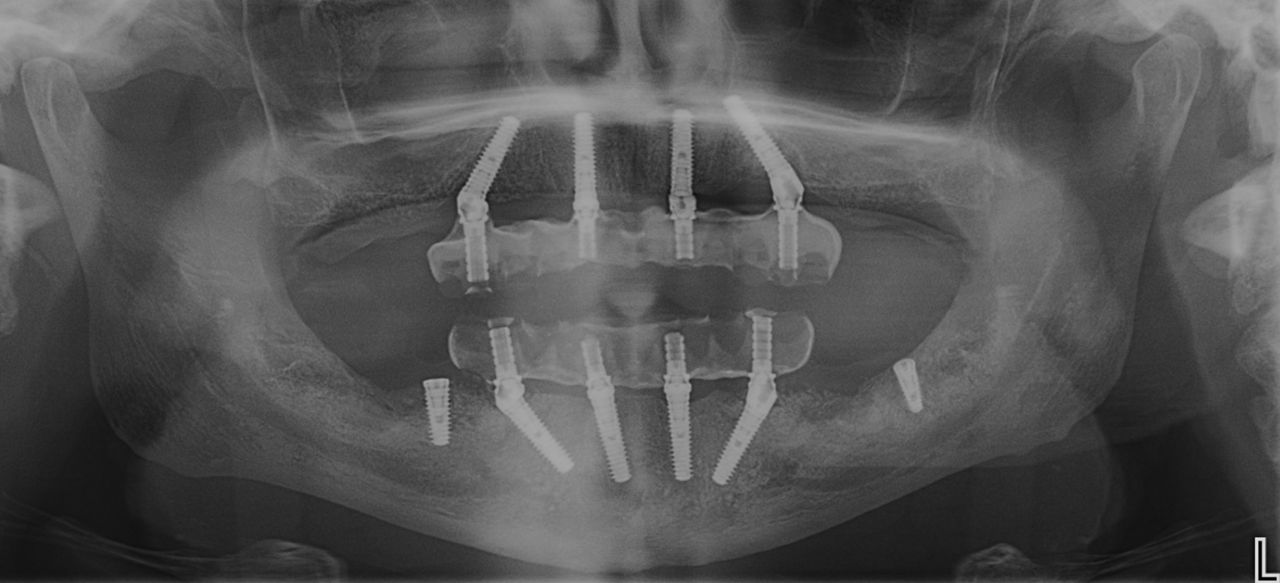

Sono il Dott. Raffaele D’Ambrosio, laureato in Odontoiatria e specializzato in Chirurgia Orale presso l’Università Vita-Salute San Raffaele di Milano. Mi occupo di riabilitazioni complesse, con particolare attenzione ai casi "con poco osso", offro soluzioni rapide e affidabili, come i denti fissi in 24 ore.

Tra le mie competenze rientrano anche l’estrazione di ottavi complessi, l’ortodonzia invisibile con Invisalign e la progettazione di protesi dentarie su misura. Grazie a un percorso di formazione continua, integro tecniche avanzate di chirurgia parodontale e implantare per garantire trattamenti efficaci e personalizzati.